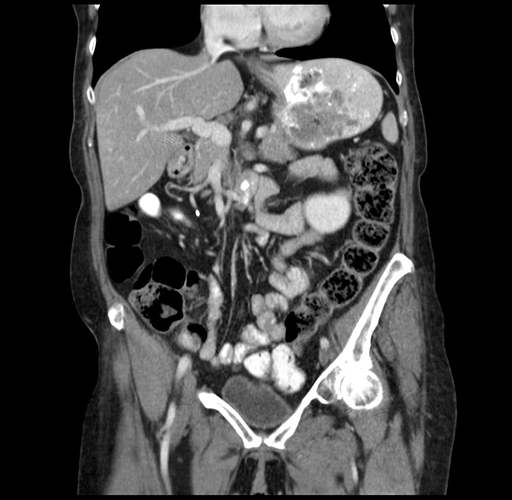

Pre-Chemo: Coronal Venous

Coronal Venous